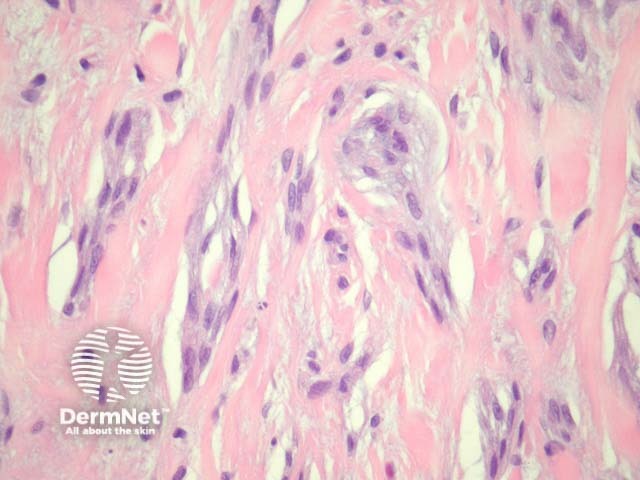

The cellular subtype of neurothekeoma is composed of a circumscribed proliferation of spindled and epithelioid cells in lobules and fascicles. Sclerotic collagen is common between the lobules (figures 1, 2, 3). Intermixed giant cells may be seen.

Figure 1

Figure 2

Figure 3